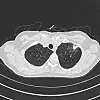

He said most of the clinic’s original patients already have had a computed tomography, or CT, scan that has revealed some sort of anomaly in their lungs. The team at UNM then plan the next course of action, such as a biopsy to determine if it is cancerous.